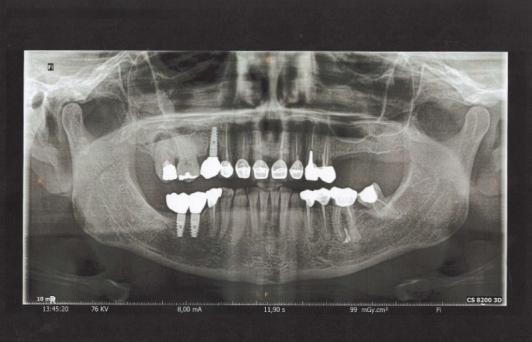

L’imagerie dentaire s’appuie sur des techniques d’imagerie conventionnelles et numériques. Pratiquée dans votre cabinet dentaire à Bruxelles, la radiographie panoramique dentaire ou radio panoramique permet d’obtenir une vue complète de la mâchoire, de la mandibule, des dents de sagesse et des structures osseuses. Chaque image radiographique contribue à un diagnostic fiable et à la planification de traitements tels que la pose d’implants dentaires, la préparation d’une prothèse dentaire ou le suivi de soins dentaires existants.

À proximité de Woluwe-Saint-Lambert et des quartiers voisins, votre clinique dentaire propose des examens radiographiques dentaires adaptés à chaque patient. La radiologie dentaire permet de visualiser les dents, le maxillaire et la mandibule avec une clarté exceptionnelle.

Les équipements d’imagerie numérique du cabinet facilitent la détection des pathologies osseuses, la préparation à la pose d’implants et la planification de prothèses dentaires.

La radiographie numérique et le scanner dentaire offrent des images détaillées des structures osseuses et faciales. Tout comme un centre d'imagerie dentaire, Dental Anspach, cabinet dentaire à Woluwe-Saint-Pierre, met la

technologie au service de la précision et du confort. L’utilisation de techniques d’imagerie assistée par ordinateur permet de visualiser les dents, les gencives et les tissus environnants. Ces examens radiologiques

contribuent à la prévention et au suivi de la santé bucco-dentaire.

À noter : Avant tout examen clinique, il est conseillé de signaler la présence de prothèses dentaires, d’objets métalliques ou d’implants afin d’assurer une radioprotection optimale et une image radiographique de qualité.